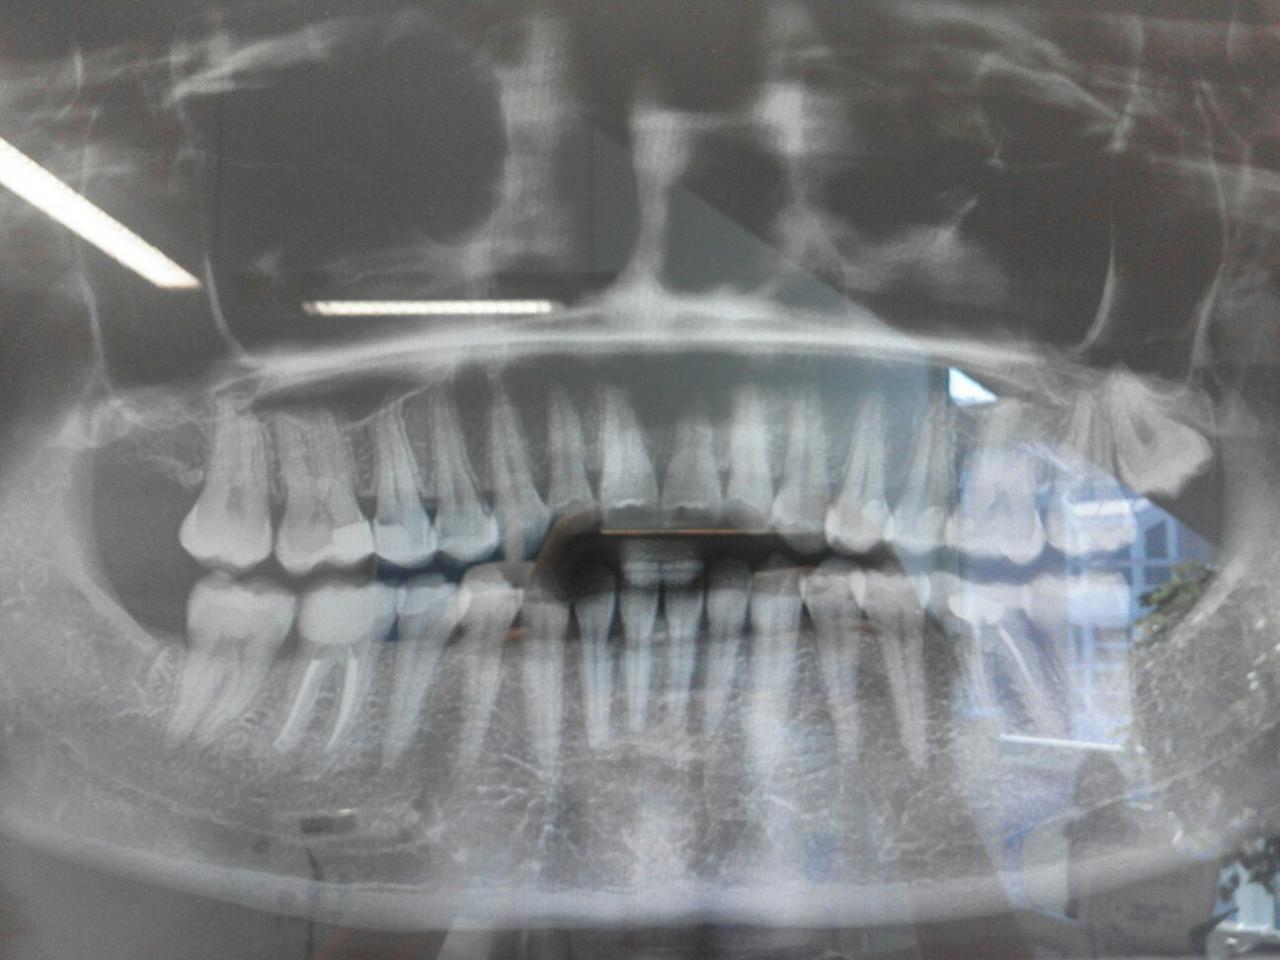

Вот на панорамном снимке хорошо видно.